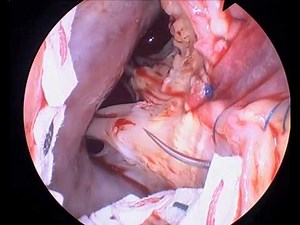

Aorta Anatomy

YouTubeCleveland Clinic